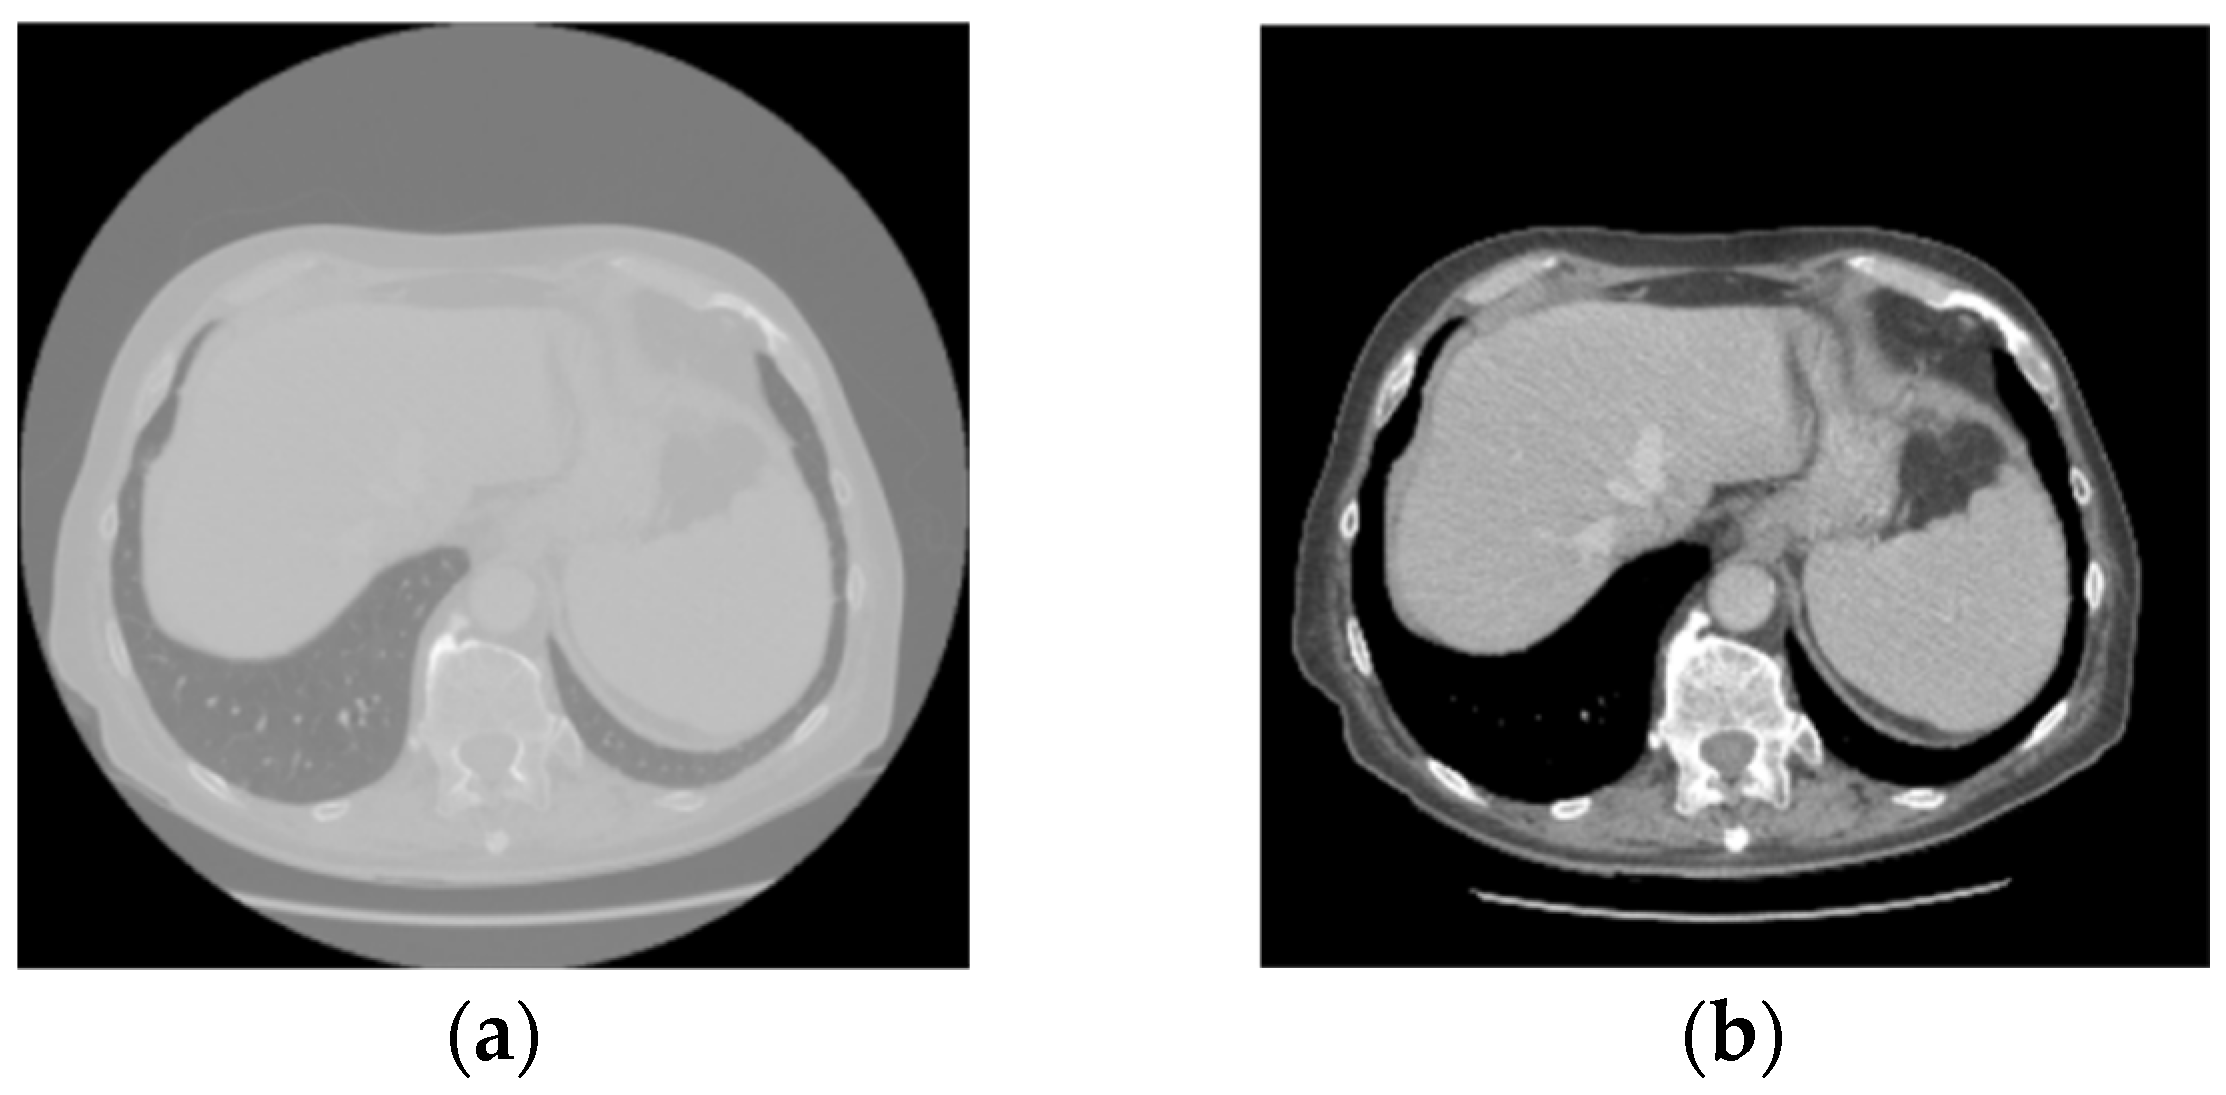

Figure 4 and Figure 5 illustrate some examples of the liver tumor segmentation results with our model from the LiTS dataset and the 3DIRCADb dataset, respectively. Visual inspection of the segmentation results reveals that the predicted tumor regions are properly aligned with the ground truth in terms of both the number of tumors and their morphology.

Figure 4. Examples of tumor segmentation results of the proposed model over the LiTS dataset. Upper: the ground truth; bottom: the predicted tumor regions.